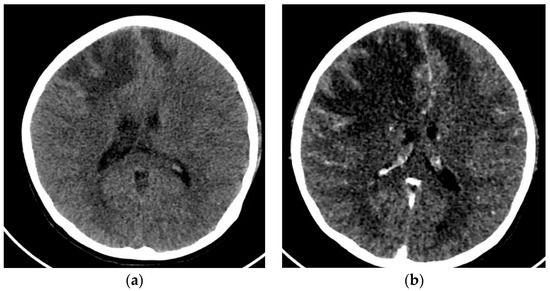

2.2. Case 2